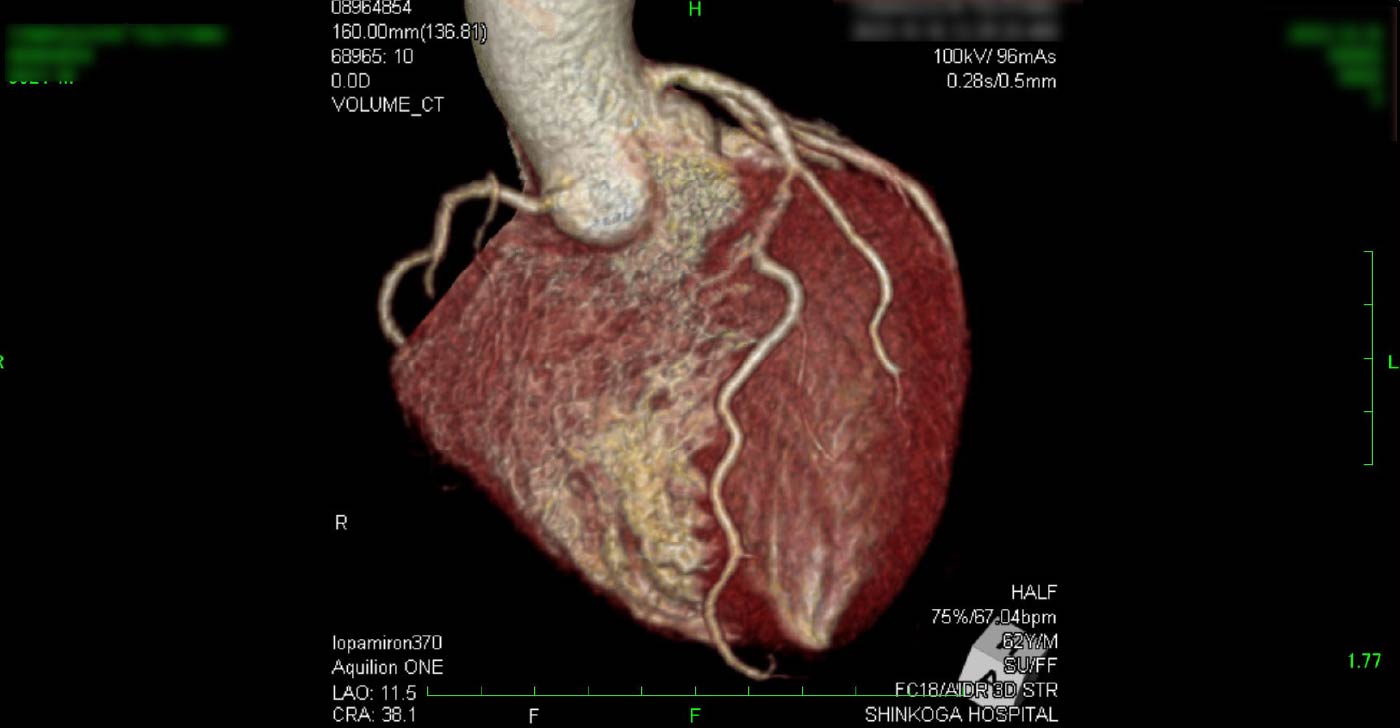

冠動脈CT

狭心症を安全に診断あるいは除外する!

連携施設の新古賀病院で速やかに実行可能です。